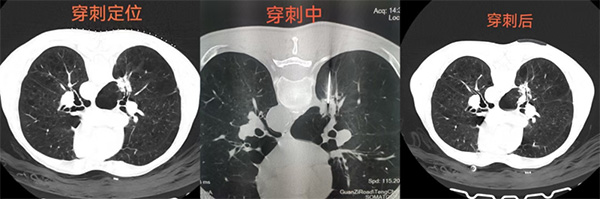

经增强CT检查发现右肺一病灶特殊,可见分叶、毛刺、胸膜凹陷、充气支气管、棘样突起征,同时病灶周围血管丰富。因患者有重度肺气肿,穿刺活检时发生大出血及气胸等并发症的风险极高。因患者及家属已是几经周折,此次非常期望能够明确诊断。经医学影像科团队反复研究病人情况、病灶特点和周围血管关系后,规划了最优穿刺路径,并制定了大出血及气胸等并发症风险应急预案。充分做好应急处置准备的情况下,在团队成员协助下,熊江主任为患者行经皮肺穿刺活检术,成功获取两条灰褐色、鱼肉样活体肺组织标本送病理科检查。手术过程顺利,15分钟时间完成,未发生任何穿刺并发症。

病检结果提示:(肺结节活检)恶性肿瘤,建议行免疫组化检查进一步诊断。最终明确了病变性质,为患者后续诊疗提供了有力依据。